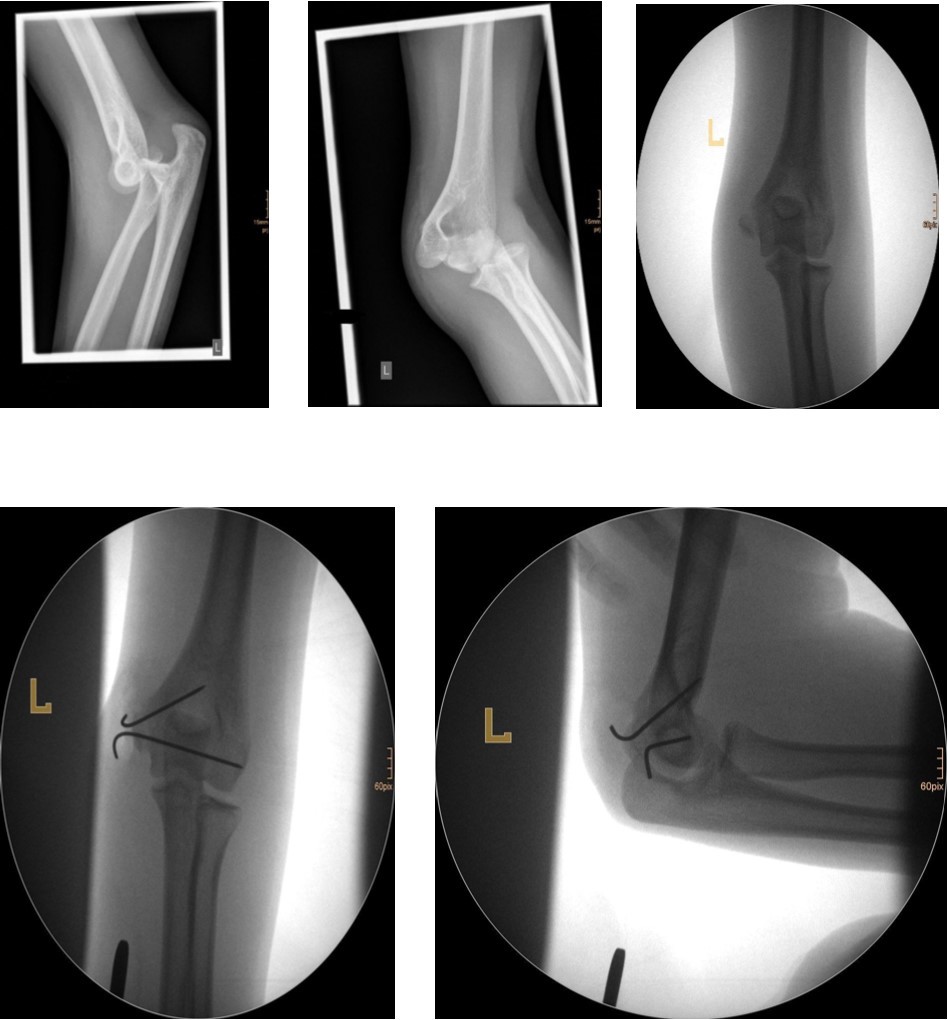

Figure 2.6 year old male patient with a dislocated right lateral condyle fracture which was treated by open reduction and osteosynthesis with a screw and a Kirschner wire (personal collection)

6 year old male patient with a dislocated right lateral condyle fracture which was treated by open reduction and osteosynthesis with a screw and a Kirschner wire (personal collection)

Non-displaced and stable fractures may be treated by cast immobilization with close follow-up, but fractures displaced >2 to 3 mm may indicate surgical fixation 7, 8. Surgical treatment can be done either by closed reduction and percutaneous osteosynthesis or open reduction and osteosynthesis. Figure 3.